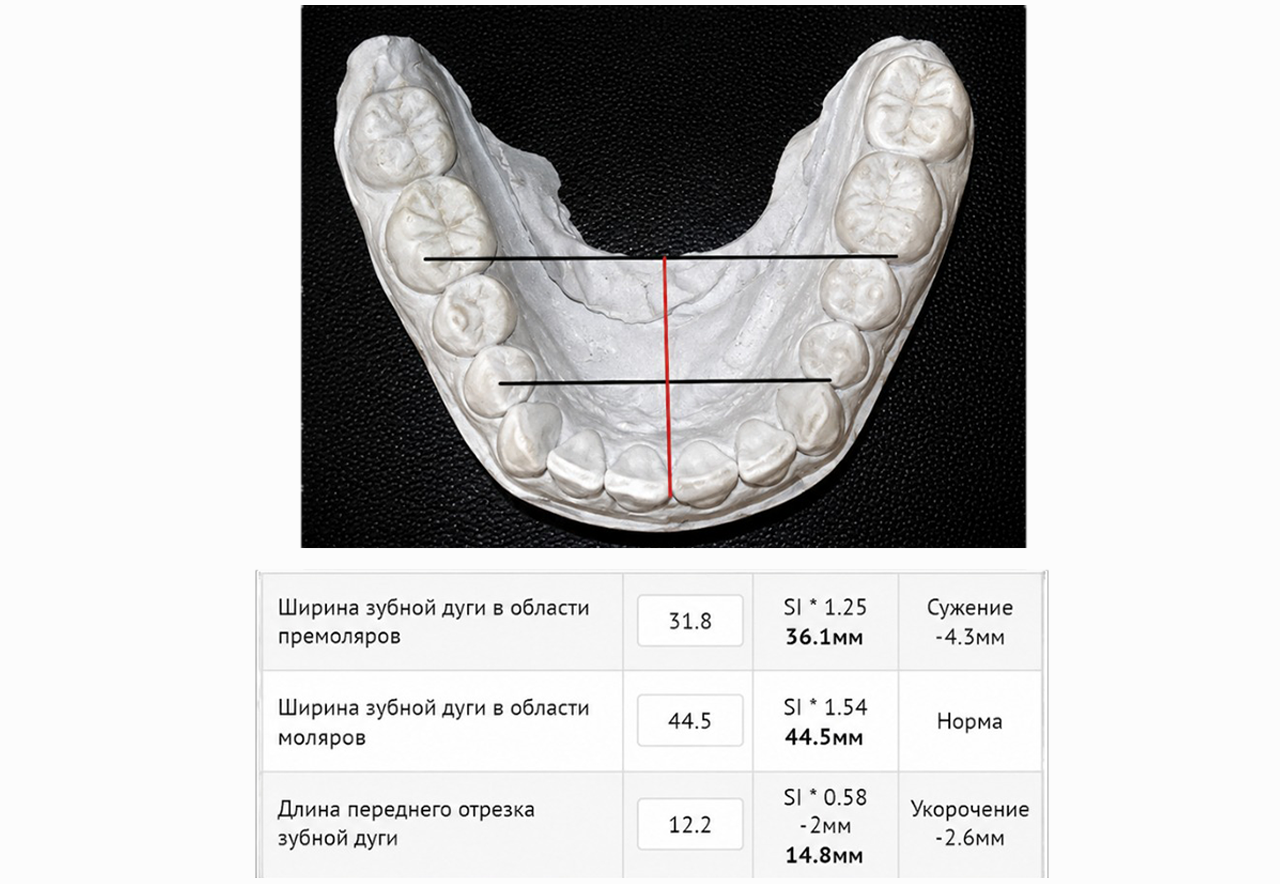

- С помощью специального программного обеспечения с математической точностью производим все рассчеты будущего лечения.

Будут произведены математические рассчеты будущего лечения